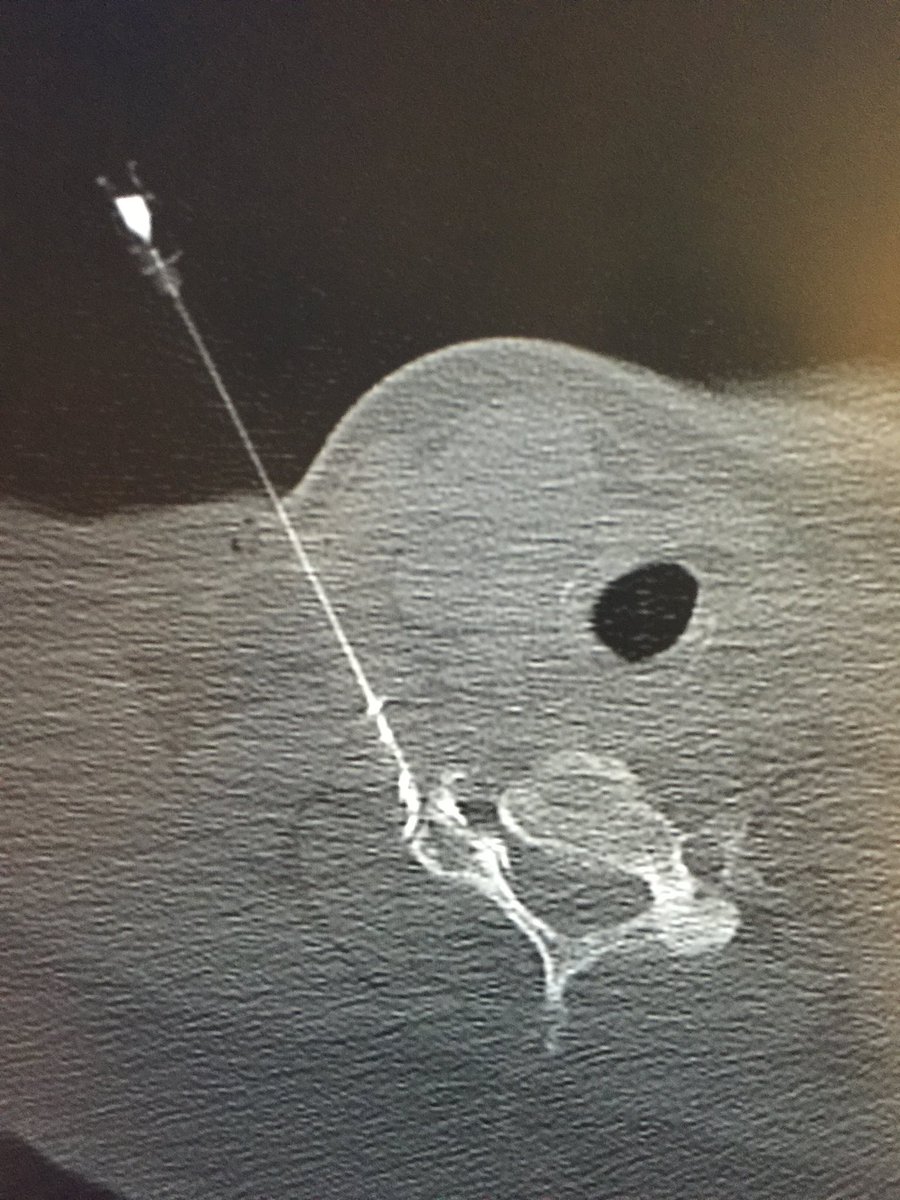

Day 5 @NHSHarlow. Our #irad team perform CT guided spinal injections for pain management. Service is popular with our patients & supported by our spinal surgeons. Photos 1)cervical interlaminer epidural 2) thoracic transforaminal 3) SIJ 4) cervical transforaminal. Zaid A H Aldin

Day 5 @NHSHarlow. Our #irad team perform CT guided spinal injections for pain management. Service is popular with our patients &amp; supported by our spinal surgeons. Photos 1)cervical interlaminer epidural 2) thoracic transforaminal 3) SIJ 4) cervical transforaminal. <a href="/ZaidAHAldin1/">Zaid A H Aldin</a>